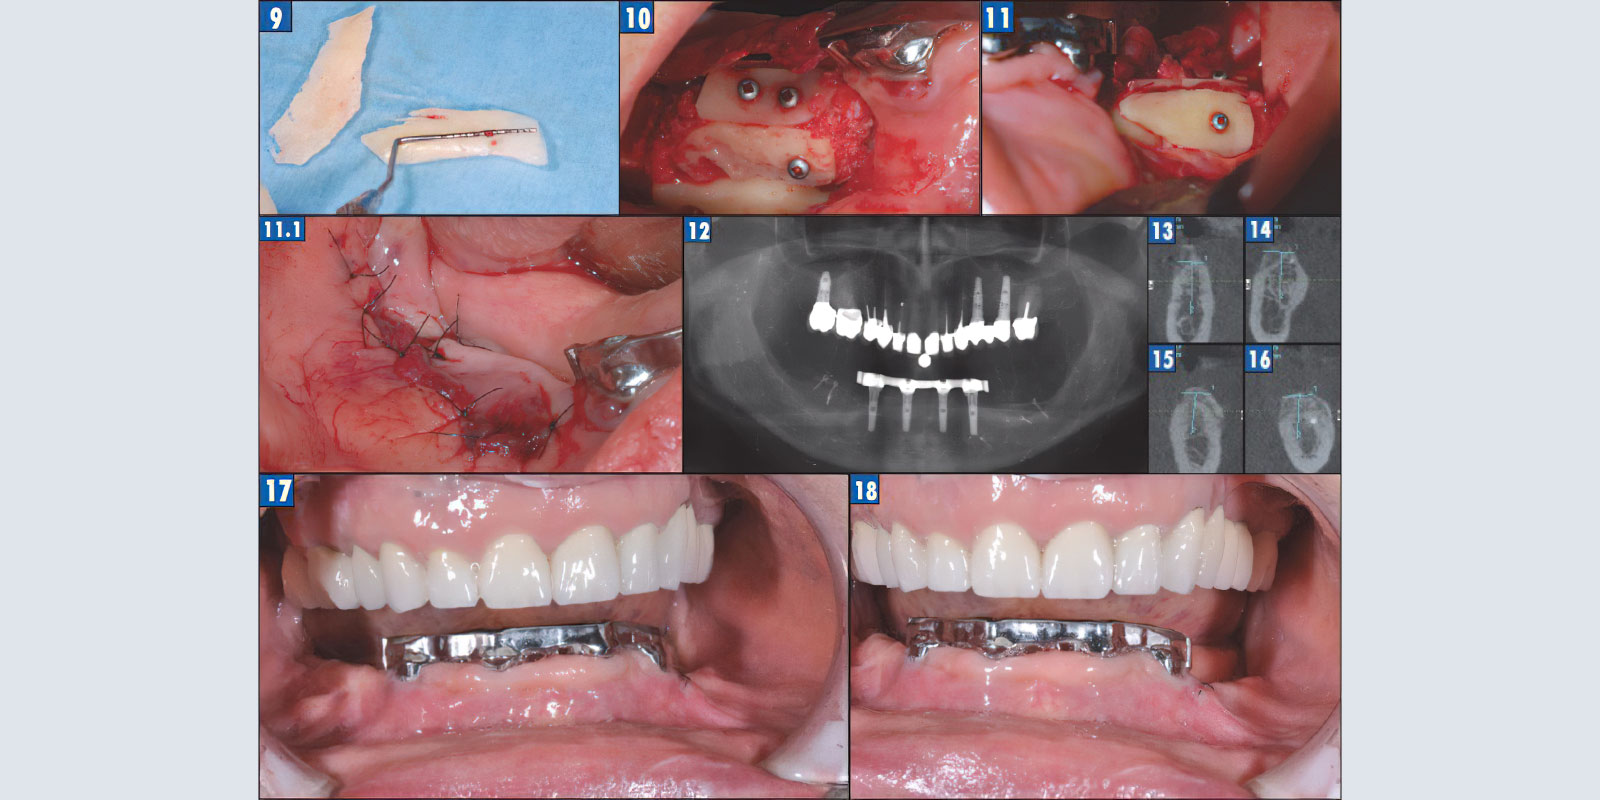

Из костных пластин сформирован каркас будущего альвеолярного отростка, пустоты плотно заполнены костной стружкой (рис. 9–11). Фиксация пластин осуществляется титановыми микровинтами. Для ушивания раны используется методика послойно ушивания. С помощью резорбируемой нити толщиной 6,0 ушивается надкостница, причем за счет широкой отслойки надкостницы практически всегда можно избежать послабляющих разрезов, нерезорбируемой нитью отдельно ушивается слизистая оболочка. В итоге получаются два уровня швов, что является дополнительной страховкой от экспозиции аугментата (рис. 11.1).

Рис. 9. Костные пластины.

Рис. 10. Пластика в IV квадранте.

Рис. 11. Пластика в III квадранте.

Рис. 11.1. Вид раны после ушивания.

Рис. 12. Ортопантомограмма через 4 месяца после пластики.

Рис. 13. Позиция 46 после пластики.

Рис. 14. Позиция 47 после пластики.

Рис. 15. Позиция 36 после пластики.

Рис. 16. Позиция 37 после пластики.

Рис. 17, 18. Состояние через 4 месяца после пластики.

Через 4 месяца после костной пластики пациентка была приглашена для полного диагностического обследования, включая и компьютерную томографию. Данные КТ свидетельствуют об успешном результате костной пластики. Сформирован объем костной ткани, достаточный для последующей имплантации (рис. 12–16). Но при этом кератинизированная десна по-прежнему отсутствует (рис. 17–18).